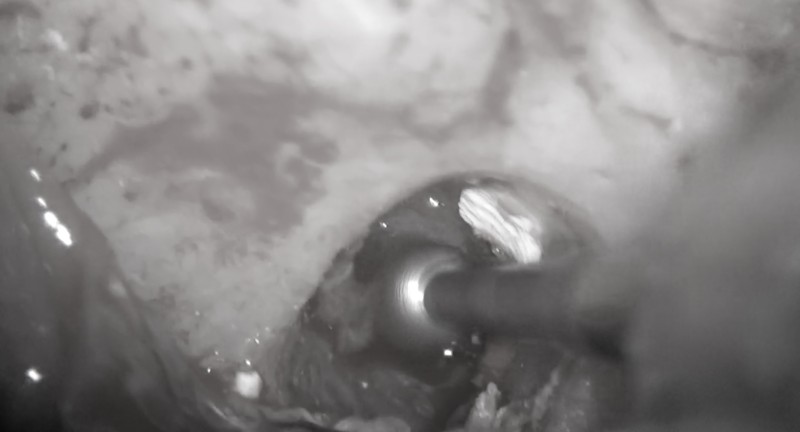

しかし、一昔前に比べ顕微鏡、ラバーダム、レーザー、高周波装置、CTなどにより根管治療の成功率は格段に向上しました。

器具が増えるということはそれだけ時間がかかりますが

きちんと時間を確保し、根の中の細菌の洗浄を行い治療を行うだけで骨の再生が起こります。